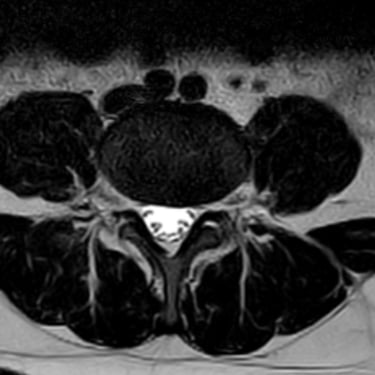

Discopatía Lumbar Degenerativa con Artrosis Facetaria | Diagnóstico por Resonancia Magnética

La discopatía lumbar degenerativa con artrosis facetaria es una causa frecuente de dolor lumbar crónico, que limita la movilidad y la calidad de vida del paciente. Esta condición combina la degeneración de los discos intervertebrales con el desgaste de las articulaciones facetarias, lo que puede generar inestabilidad y compresión nerviosa. La resonancia magnética (RMN) es la herramienta diagnóstica más precisa, ya que permite identificar deshidratación y colapso discal, hipertrofia facetaria, estenosis foraminal y signos de inflamación. El diagnóstico temprano es fundamental para establecer un tratamiento adecuado, que puede ir desde medidas conservadoras hasta técnicas quirúrgicas mínimamente invasivas.